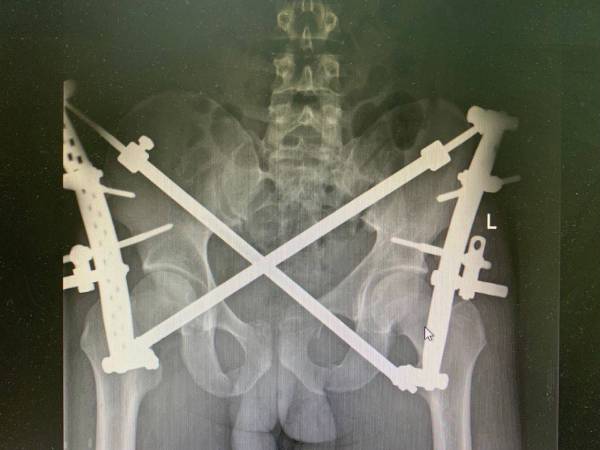

У него была сочетанная травма, политравма: множественные закрытые переломы костей таза, рёбер, обеих голеней и стоп.

Всего в республиканской больнице мужчине выполнили четыре операции. В самой обширной из них было задействовано одновременно четыре травматолога, два анестезиолога. Специалистам необходимо было анатомически точно сопоставить фрагменты повреждённых костей, а затем зафиксировать специальными имплантами.